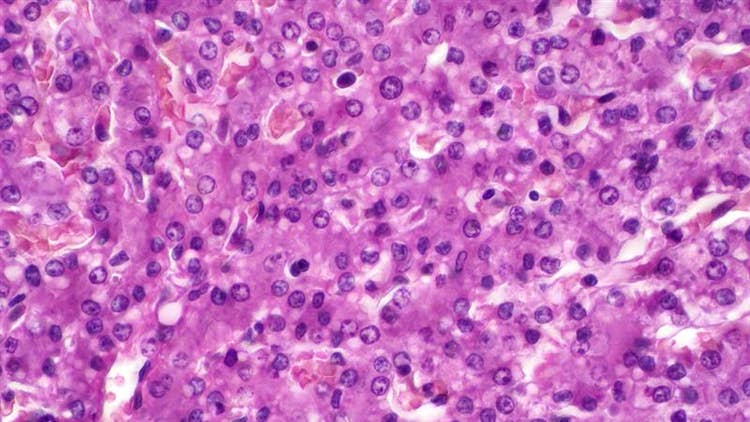

In an AI-assisted screening study, researchers used 3D liver microtissues (3D Insight™ Liver Model) to develop an imaging-based in vitro assay for toxicity evaluation. Using a cell painting assay, a multiplexed fluorescent imaging technique was applied to capture key phenotypic changes. ImageXpress HCS.ai High-Content Screening System from Molecular Devices generated thousands of images per compound treatment, which were analyzed using machine learning by IN Carta software to identify early compound effects.